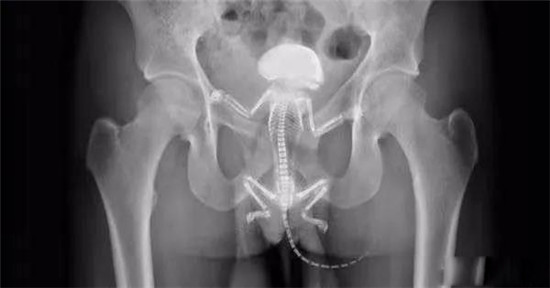

一只松鼠在直肠里。

病人和他的这只出现在直肠里的松鼠在病人来医院一周前的合照。

松鼠把他的直肠抓破了,最后松鼠死在他的直肠里,医生只好给他开刀取出来了。